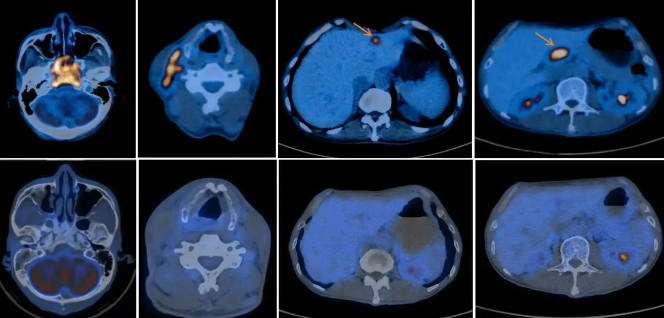

鼻咽癌伴颈部淋巴结、胰头淋巴结及肝转移治疗前后对比